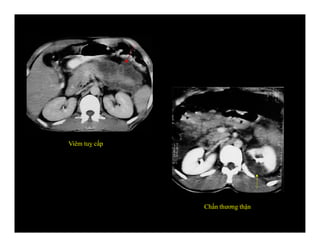

Viêm tuỵ cấp

Chấn thương thận

Viêm tuỵ cấp Chấnthương thận